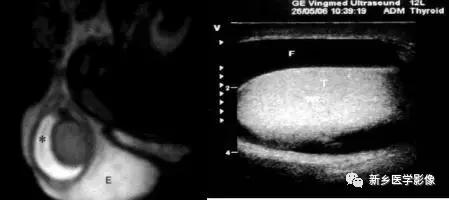

MR:*丸睾**炎T2WI不仅要低信号,增强扫描不均匀强化,合并鞘膜腔积液

MR:精原细胞瘤各信号偏低、均匀、散在,恶性病变,信号可不均;非精原细胞瘤信号不均

MR

急性扭转的*丸睾**体积增大,可见出血

4.MR显示中等至高信号匍匐区长静脉,静脉内血流缓慢T2WI可表现为高信号。

MR:沿*丸睾**上纵膈方向会出现*丸睾**网多发小管膨胀或扩张,相对正常*丸睾**实质T2WI上呈等或高信号。增强扫描扩张的充满液体的管道不强化。